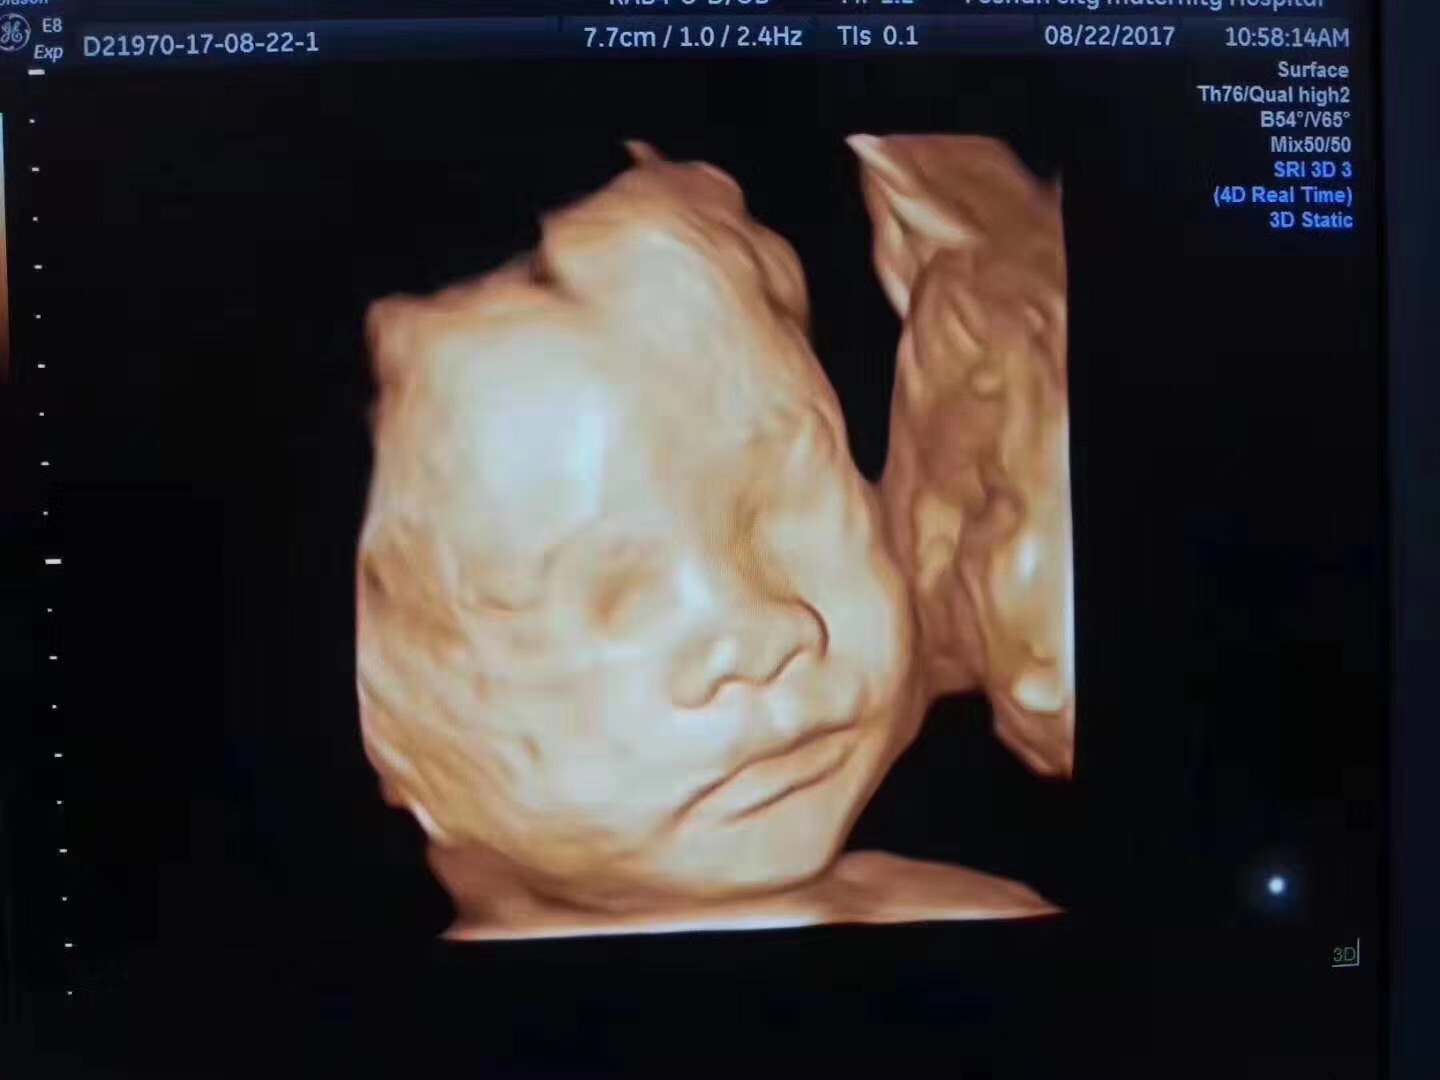

四维彩超的全称是四维彩色超声诊断仪,是现代先进的彩色超声设备。

四维彩超能够表面成像,更加清晰的筛查胎儿的四肢发育是否畸形,是否脑膜膨出,是否唇腭裂、是否脊柱裂等先天畸形,及早发现并及早做出解决方案。

四维彩超什么时间做最好?

准妈妈一般在怀孕22-26周的时候做四维彩超。因为怀孕22周以前胎儿的器官、四肢还没有发育完全,此时检查结果准确性低。

怀孕22周以后胎儿的各个器官发育良好,这个时候准妈妈就可以通过四维彩超来检测胎儿是否健康了。

到了怀孕24周左右,这个时候胎儿的结构已经形成。胎儿的大小以及羊水适中,在宫内的活动空间也比较大,胎儿骨骼回声影响比较小,图像也比较清晰。所以医生一般会建议准妈妈在怀孕22-26周的时候做四维彩超。